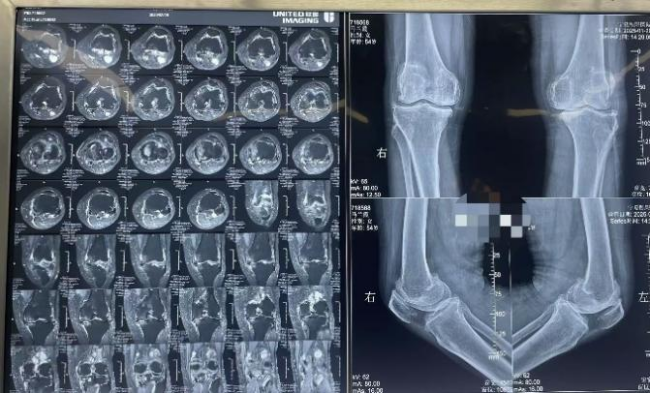

患者马女士,今年54岁,被双膝关节疼痛不适困扰长达10余年,近2年症状愈发严重,日常行走和生活自理都受到极大影响。慕名来到我院就诊后,我院外科团队迅速对马女士的病情展开全面、细致的检查,并进行了深入的术前讨论。经诊断,马女士患有严重的膝关节骨关节炎,关节软骨磨损严重,保守治疗已无法有效缓解症状,膝关节置换手术成为改善她生活质量的唯一选择。

为确保手术安全与效果,外科团队组织多学科专家会诊,结合马女士的具体情况,制定了一套科学、合理的手术方案。手术过程中,主刀医生凭借精湛的技术和丰富的经验,精准操作每一个步骤。整个手术顺利进行,出血极少,患者生命体征全程平稳。麻醉苏醒后,患者安返病房,医护团队立即给予对症治疗及专科护理。术后第二天,便指导患者借助助行器进行适当活动。目前,马女士病情稳定,身体恢复状况良好,患者及家属对我院的医疗服务高度赞誉,对手术效果十分满意。